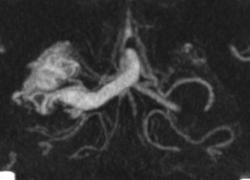

Я чуть увеличил фрагменты изображений с "патологическим состоянием"

Очень наглядна видна сосудистая мальформация.

Питание идет из гипертрофированных задней мозговой и средней мозговой артерий (красные стрелки), дренирование в основном в верхний сагиттальный синус (синий кружок). Дренирующая вена - синие стрелки.